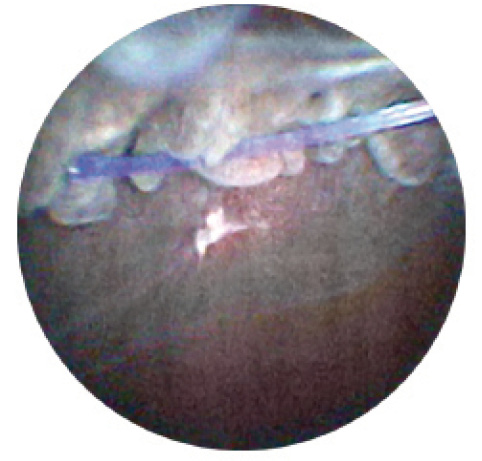

The 23-gauge endoscope is also useful for treating uveitis-glaucoma-hyphema (UGH) syndrome, which is most commonly caused by malposition of an IOL, with resultant contact with delicate uveal tissue. The causative pathology is often located just posterior to the iris. Direct visualization of this region can be helpful in diagnosis and treatment of the condition (Figures 1 and 2).

Figure 1. Endoscopic image showing tip of haptic and hemorrhage site.

Patient management in UGH can prove difficult, as the syndrome is characterized by chronic episodes of hyphema, ocular inflammation, and elevated intraocular pressure. Traditionally, anterior segment ultrasound biomicroscopy has been performed for visualization of the IOL, iris, and sulcus. If this technology is not available or is inconclusive, surgical intervention for hyphema or vitreous hemorrhage using endoscopy can greatly improve outcomes. In some cases, direct visualization of the haptic can allow repositioning of the IOL without explantation. Similarly, the 23-gauge endoscope may improve outcomes in vitrectomy for retained lens fragments, allowing a more thorough anterior vitrectomy and removal of lodged lens fragments in this region.